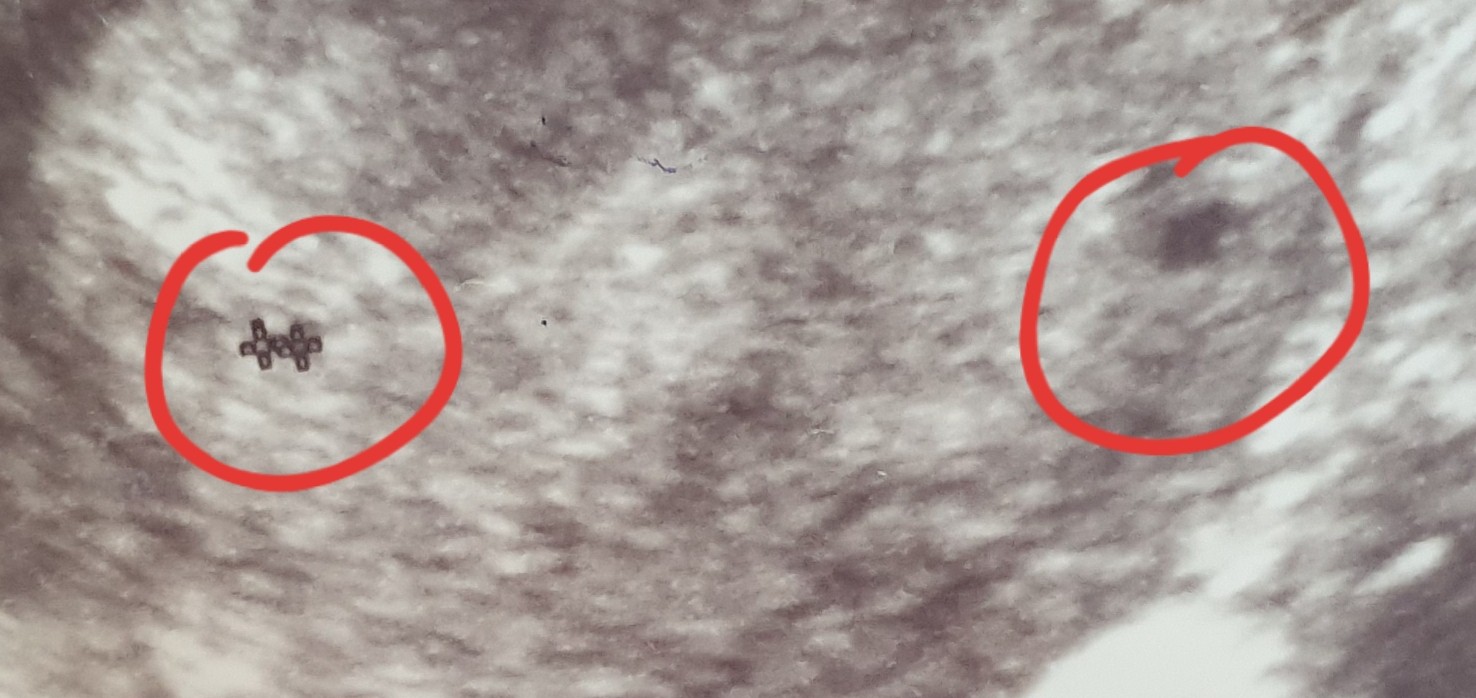

Hej Mamusie bliźniaków. Pierwsze usgz 5 tyg ciazy drugie z 6 tygodnia ciazy. Czy to są 2 pęcherzyki ciążowe? Czy mam jakieś urojenia? Lekarz nic nie mówił Ale za to przepisał duphastpn i luteine A przy pierwszej ciazy tylko luteine. Dziękuję Wam za odpowiedź. Może pamiętacie swoje usg z początków. :D

Załączniki

• 20210512_155115.jpg

20210512_155115.jpg

74,6 KB · Wyświetleń: 105